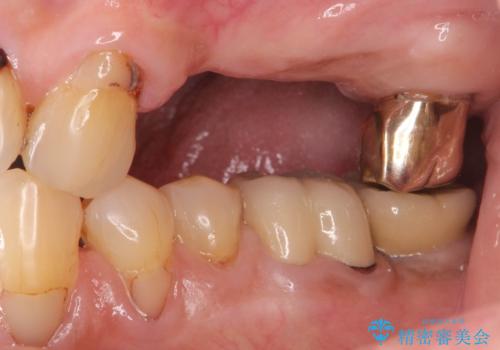

- 奥歯を失い半年間入れ歯を使用してみたが、とにかく咬めない、食事を楽しむことができない!と

咬合機能の回復を求めて来院されました。

入れ歯とは比べものにならないくらいしっかりと噛めるようになり、大変喜んでいただくことができました。